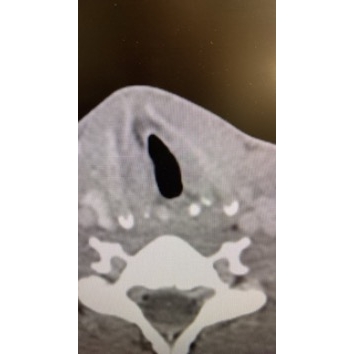

Odynophagia And Dyspnea In A College Basketball Player - Page #3 | |||